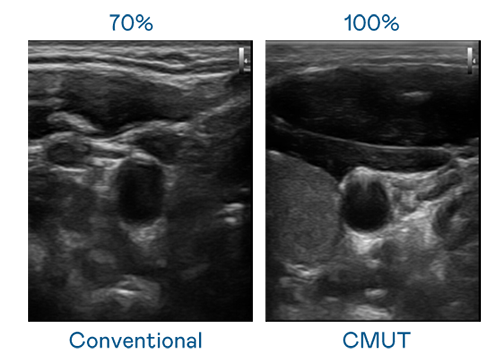

CMUT 技術是一種用電容式微機電元件來產生超音波訊號的技術。與傳統 PZT 壓電式技術相比,CMUT 頻寬增加 30%,更寬頻的超音波訊號讓影像解析度大幅提升,是實現高影像品質醫療超音波掃描、促進精準醫療發展的關鍵技術。

超音波影像的解析度高低,首先取決於探頭能發出的訊號頻寬。问鼎28 CMUT 可提供高清晰的超音波訊號,提供高頻寬、高靈敏度、影像紋理細節更高的超音波影像,協助醫護人員縮短影像判讀時間及利用精準的醫療影像進行診斷。